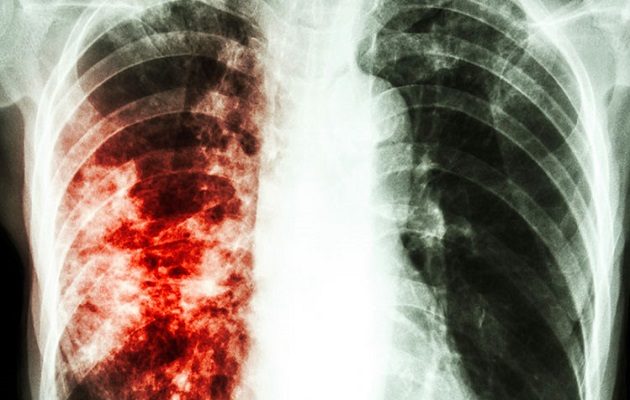

La mayor cantidad de casos  este año se registra en San Miguelito. Foto: Redes Sociales

El camino hacia la eliminación de la tuberculosis presenta diferentes desafíos y uno de ellos es la tuberculosis drogorresistente (aquella resistente al tratamiento).

De acuerdo con la Organización Mundial de la Salud (OMS), el bacilo de la tuberculosis puede volverse resistente a los antimicrobianos utilizados para curar la enfermedad.

El mal manejo del tratamiento antituberculoso y la transmisión de persona a persona explican la propagación de la tuberculosis multirresistente.

De acuerdo con información suministrada por el Programa Nacional de Tuberculosis del Minsa, en lo que va del 2022 se registran  182 casos en el país.

San Miguelito con 29 casos, Bocas del Toro con 28 y Panamá Metro, con 26 son las regiones con mayor número reportado de casos. Mientras que  Herrera, Coclé y Los Santos,  con 1 caso, son las que menos reportes contabilizan.

La  tuberculosis es una enfermedad bacteriana que suele afectar los pulmones, pero también puede impactar en la salud de los ganglios linfáticos, los riñones, los huesos y las articulaciones.